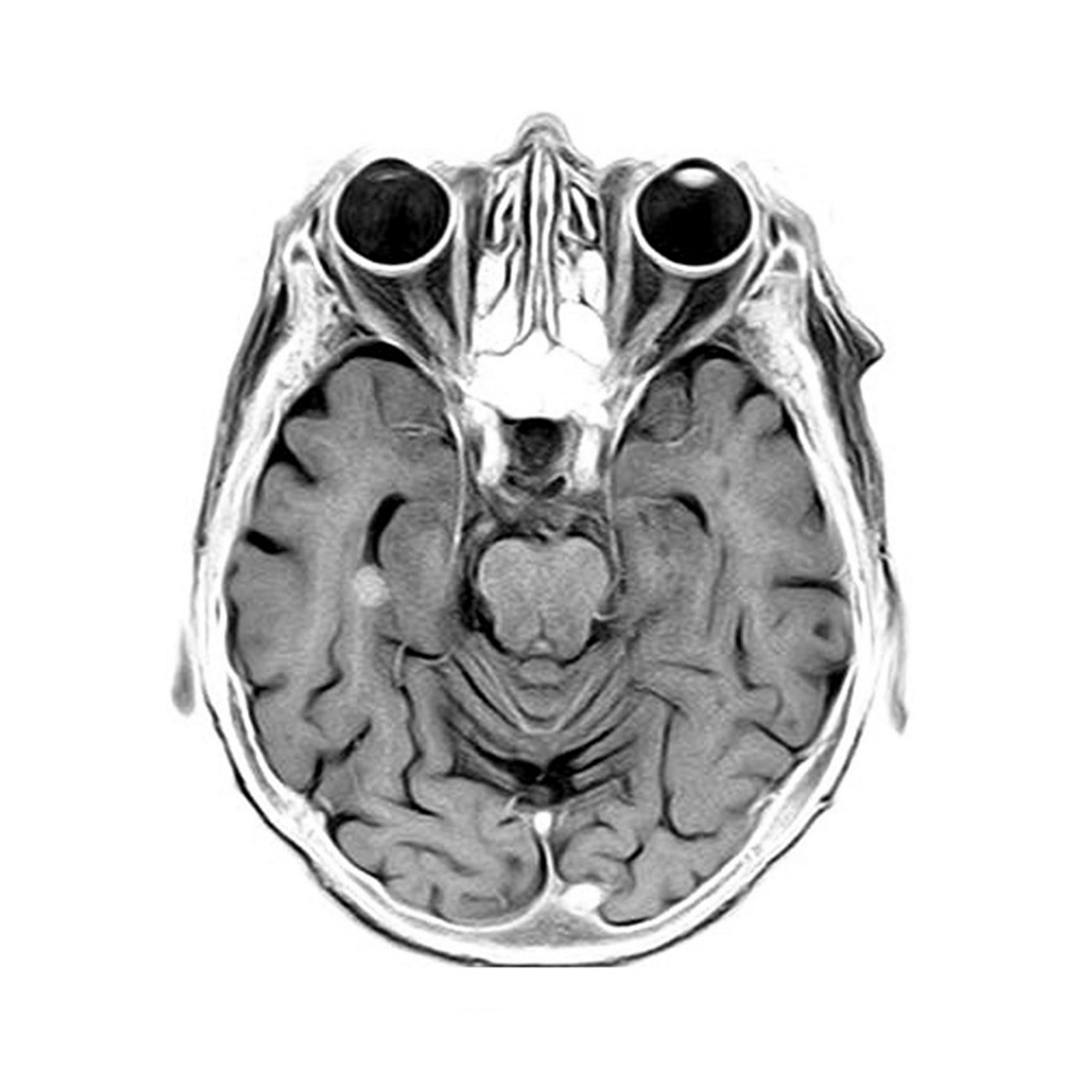

From a conceptual perspective the gamma knife (stereotactic radiosurgery) is the next step from targeted radiotherapy – by focusing hundreds of low intensity radiation beams, high intensity radiation can be delivered with micron accuracy, vaporizing tissue at the point of convergence.

Not only is the gamma knife non-invasive but can treat multiple metastatic lesions in a single day-only procedure. Although mostly seen in the field of neurosurgery, the gamma knife will likely play a significant role in multiple specialties.